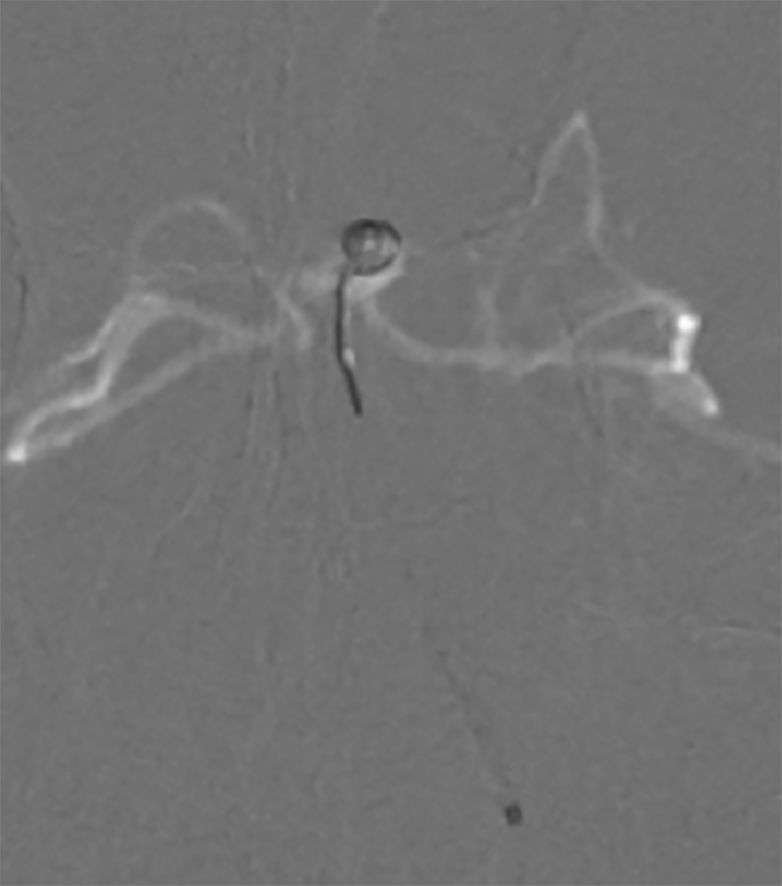

5. 调整至合适的工作角度后,路径图引导下,Synchro(0.014,200 cm)微导丝携Echelon-10微导管超选进入左侧小脑上动脉瘤(图10微导丝到位,图11微导管到位)。

图10 微导丝到位 图11 微导管到位

6. 多个投射角度辅助下,将数枚弹簧圈枚植入动脉瘤内(图12)。

图12